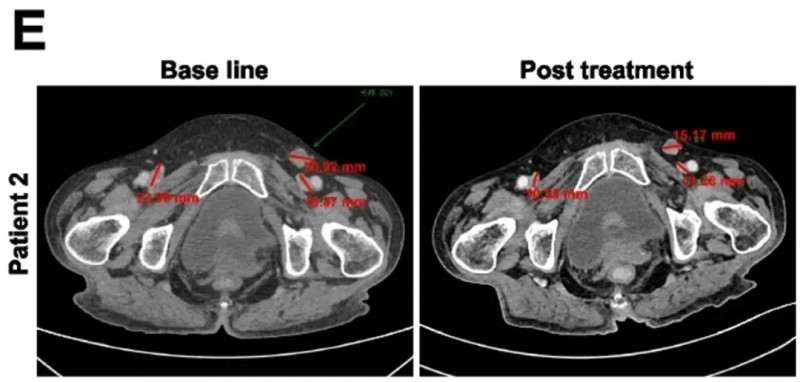

近期,世界知名期刊《Nature Medicine》报道了一项新型PSCA-CAR-T细胞疗法的首次人体1期临床试验(NCT03873805)。该试验共入组14例患者,均为PSCA阳性的转移性去势抵抗性前列腺癌(mCRPC)——癌细胞已扩散至前列腺外,且对激素治疗耐药,临床已无更优治疗方案,最终接受CAR-T细胞回输治疗。

结果显示:DL1、DL2、DL3三个剂量组患者的6个月生存率分别为33%、67%、40%。

值得关注的是,两例患者的治疗效果尤为亮眼,具体疗效如下:

第一例为DL3剂量组患者(UPN394),其肝转移负荷实现放射学改善,但未达到PSA反应;CT扫描清晰呈现了输注前的肝转移灶,以及输注PSCA-CAR-T细胞1个月后的疾病反应(详见下图c)。

▲图源“Nature Medicine”,版权归原作者所有,如无意中侵犯了知识产权,请联系我们删除

另一例为前列腺癌伴胰腺转移患者(UPN388):输注PSCA-CAR-T前后的CT复查显示,输注前病灶大小为40.2×24.8mm,输注后1个月病变完全消退、已无法测量(详见下图e);尽管因存在骨转移,RECIST评估结果为“病情稳定”,但患者软组织转移灶的放射学表现已有所改善(详见下图b)。